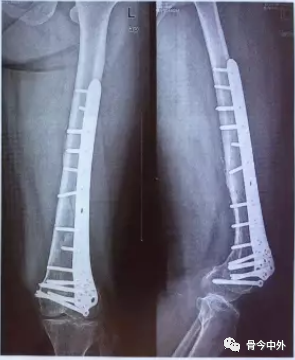

# علاج كسور عظمة الترقوة بتقنية التدخل الجراحي المحدود (MIPO): دليل شامل تُعد كسور عظمة الترقوة من الإصابات الشائعة في …